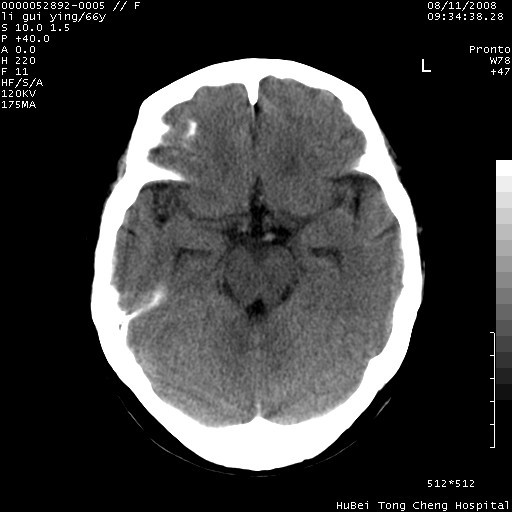

以下是引用代课学生在2008-8-12 9:48:00的发言:[br]考虑出血灶可能性大。

以下是引用yangyudong333在2008-8-12 12:22:00的发言:[br]1.病灶呈圆形[br]2.周围无水肿带[br]3.密度不均匀,内有点状钙化[br]4.无占位效应[br] 考虑良性占位性病变,血管瘤可能性大